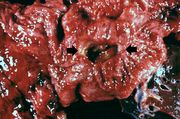

| 03:38, 19 August 2013 | IPLab3Tuberculosis1.jpg (file) | 51 KB | Seung Park | This is a gross photograph of a lung containing a nodular lesion at the lung apex (arrows). Note that the lesion appears solid and has a whitish coloration indicating considerable fibrous connective tissue. This is a healed granuloma due to primary tub... | 1 | |